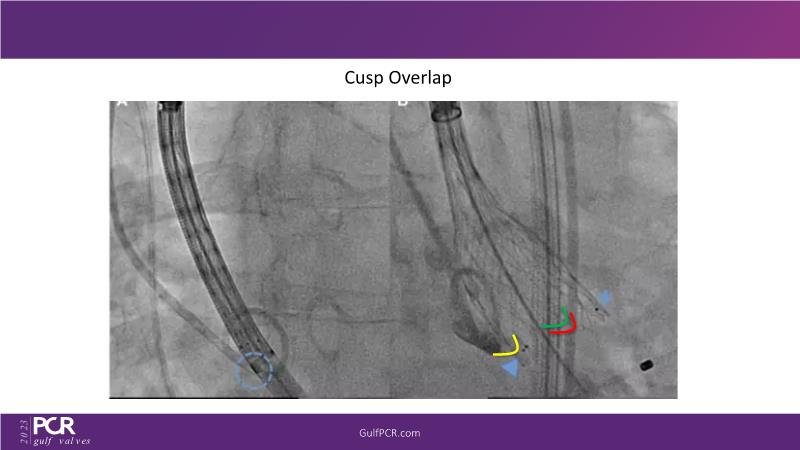

The primary focus of this GulfPCR-GIM 2023 session revolves around pre-procedural planning considerations, valve selection, and managing complex anatomies using both traditional self-expanding valves and the Evolut FX system. Additionally, the session aims to explore the work-up protocol for patients grappling with severe AS and advanced CKD, elucidate the algorithm for selecting the appropriate TAVR platform, discuss strategies to reduce contrast utilization, and highlight the distinctive advantages offered by the Evolut FX system.

• To discuss valve choice in challenging anatomies

• To learn more about optimization of valve deployment